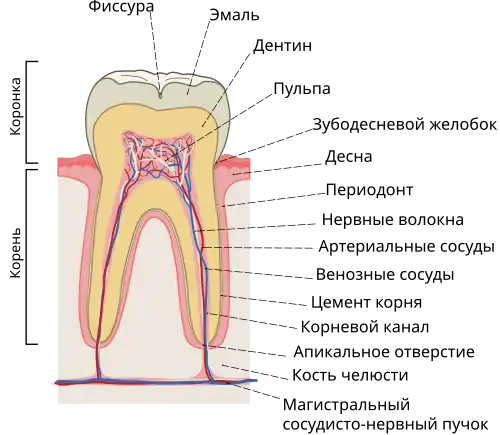

Корнево́й кана́л зу́ба (лат. canalis radicis dentis) — представляет собой анатомическое пространство внутри корня зуба. Данное природное пространство в пределах коронковой части зуба состоит из пульповой камеры, которая соединяется одним или несколькими основными каналами, а также более сложными анатомическими ответвлениями, которые могут соединить корневые каналы друг с другом или с поверхностью корня зуба.

Внутри зуба располагается полость, состоящая из пульповой камеры и корневого канала зуба. Через специальное (апикальное) отверстие, расположенное в верхушке корня (части зуба, расположенной глубоко в альвеоле и покрытой десной), в зуб проникают артерии, которые доставляют все необходимые вещества, вены, а также нервы, осуществляющие иннервацию зуба. Количество корней зависит от формы и положения зуба в ротовой полости: резцы и клыки имеют единственный корень, премоляры 1—2, число корней у моляров 3—4, а у зубов мудрости в редких случаях достигает пяти[1]. Однако, количество основных корневых каналов зуба далеко не всегда коррелирует с количеством корней. Зачастую корни зуба, кроме апикальных, имеют дополнительные отверстия — канал может раздваиваться как возле пульпы, так и в районе вершины корня (апекса): в таком случае корень обладает двумя верхушками. Встречаются варианты параллельного расположения каналов в пределах одного корня. Например, однокоренной клык чаще всего двухканальный и только в 6% случаев имеет единственный канал. В свою очередь, центральный нижний резец в 2/3 случаев имеет два канала. Корневые каналы зубов зачастую обладают неправильной формой, изогнуты и имеют узкий ход, что существенно затрудняет процесс их пломбировки[2]. Сложный комплекс разветвлённых, извитых, пересекающихся основных и дополнительных каналов, принимающих различные формы и вариабельные конфигурации, не всегда описанные в учебниках анатомии, получил название система корневых каналов[3].